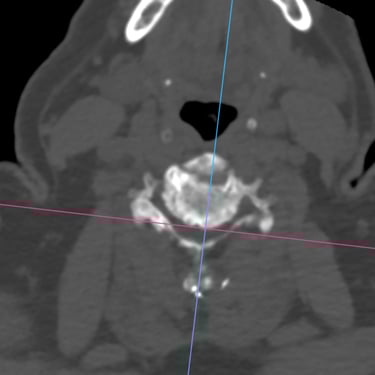

🧠Fractura vertebral lumbar osteoporótica en el adulto mayor: manejo con vertebroplastia percutánea.

Las fracturas vertebrales osteoporóticas en adultos mayores son una causa frecuente de dolor lumbar incapacitante. La vertebroplastia percutánea es un procedimiento mínimamente invasivo que permite estabilizar la vértebra afectada mediante la inyección de cemento óseo, logrando alivio del dolor y recuperación funcional temprana en pacientes seleccionados.